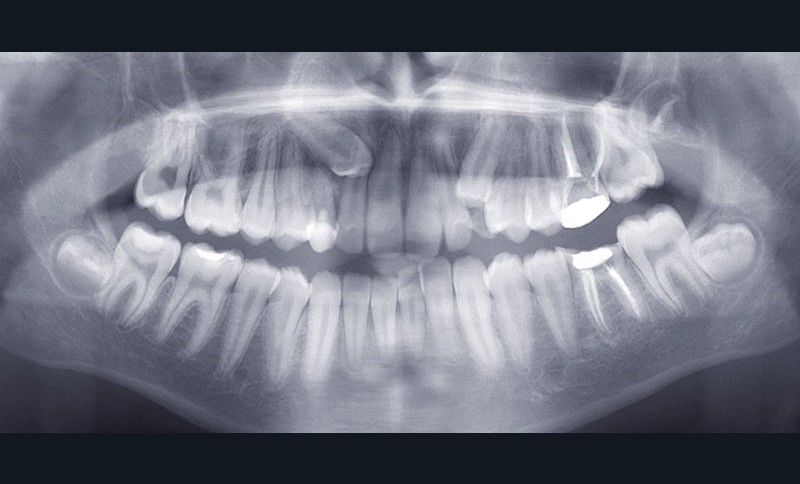

Examen radiographique

Le bilan rétro-alvéolaire révèle une atteinte du plancher radiculaire de 26 et 36 (fig. 10 et 11).